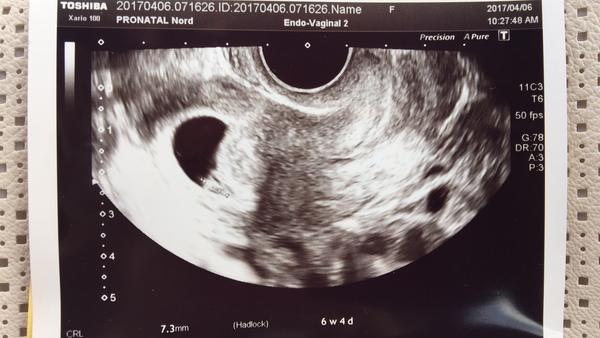

@kathlinkata tvoje první fotecka👍❤a je tam teda jen jedno?

@pajala je tak jen jedno 😘 bylo to uzasny necekala sem ze budu brecet, dostalo me to tam